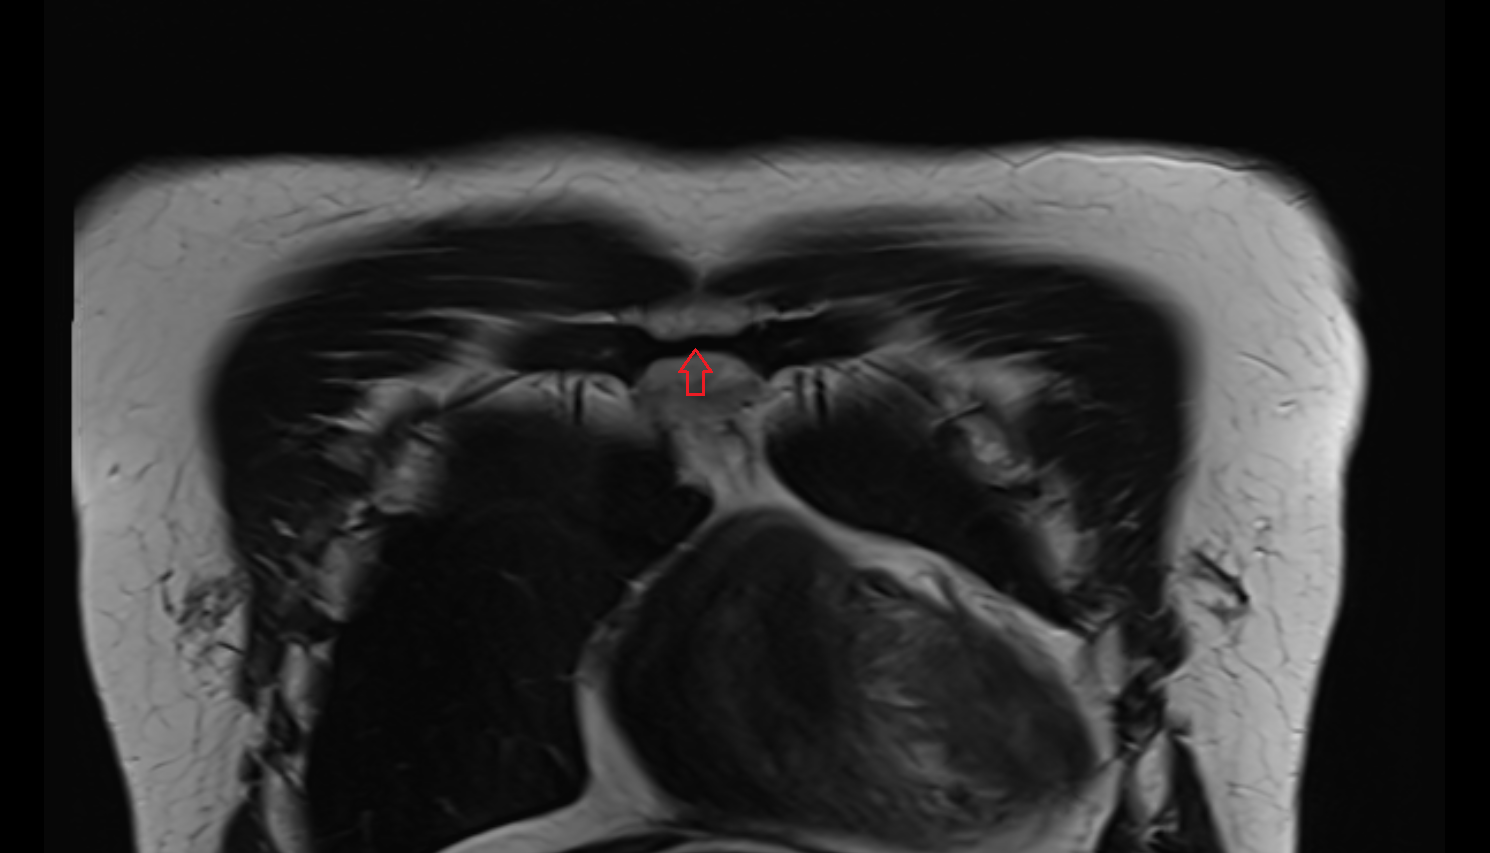

- Knee Joint